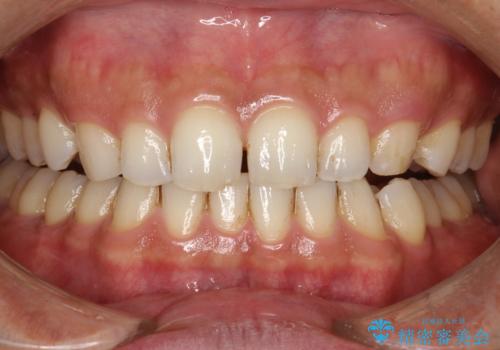

歯と歯の間の着色をPMTCでできる限り除去

- 歯と歯の間の着色を綺麗にしたいとのことで来院されました。PMTC60分で取れる範囲の着色や歯石などの除去を行いました。

毎日丁寧に歯磨きをしていても、日常生活での飲食物などにより着色してしまうことはあります。PMTCでは、歯の表面の凸凹にミネラルを補給して、ツルツルの表面に仕上げます